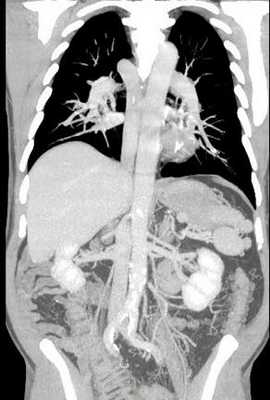

При полисплении, или левом изомеризме [12] возможны следующие аномалии развития: оба легких состоят из двух долей, оба предсердия имеют морфологию левого, выявляются множественные селезенки, аплазия нижней полой вены с дренированием в непарную вену (рис.3), врожденные пороки сердца, удвоение верхней полой вены или её отсутствие.

Рис.3. СКА сосудов брюшной и грудной полостей (справа – фронтальный, слева - сагиттальный срез). Аплазия предпочечного и печеночного отделов нижней полой вены с дренированием в непарную вену, полиспления.

При асплении, или правом изомеризме [12] наблюдаются следующие аномалии развития: оба легких состоят их трех долей, оба предсердия имеют морфологию правого, отсутствует венечный синус, отсутствует селезенка, печеночные вены могут впадать в левое предсердие, наблюдаются удвоение нижней полой вены и верхней полой вены, врожденные пороки сердца. При асплении пороки сердца более тяжелые, чем при полисплении.